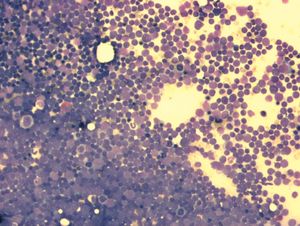

급성 림프모구 백혈병(ALL)은 림프구의 비정상적인 증식으로 발생하는 혈액암의 일종이다. 초기 증상은 비특이적이며, 피로감, 발열, 멍, 뼈 통증 등이 나타날 수 있다. ALL은 유전적 돌연변이로 인해 발생하며, 특정 유전 증후군이나 환경적 요인도 위험을 증가시킬 수 있다. 진단은 혈액 검사, 골수 생검, 면역 표현형 분석, 세포 유전학적 검사를 통해 이루어진다. 치료는 화학 요법, 방사선 치료, 표적 치료, 면역 요법 등이 사용되며, 최근에는 키메라 항원 수용체 T 세포(CAR-T) 치료법도 개발되었다. 소아 ALL은 치료 성공률이 높지만, 성인의 경우 예후는 환자의 특성, 질병의 특징, 치료 반응에 따라 다르다.

급성 림프모구 백혈병(ALL) 진단은 철저한 병력 청취, 신체 검사, 전체 혈구 수(CBC) 및 혈액 도말 검사로 시작된다. 일반적인 질병에서도 급성 림프모구 백혈병과 비슷한 증상이 나타날 수 있지만, 증상이 지속되거나 원인이 불분명하면 암을 의심해야 한다. 병력 및 검사 결과는 급성 림프모구 백혈병에만 나타나는 특징이 아니므로 추가 검사가 필요하다.[113] 순환 혈액 내 백혈구와 림프모세포 증가는 골수에서 림프 세포가 빠르게 생성됨을 의미하며, 급성 림프모구 백혈병을 의심할 수 있다. 초기 백혈구 수는 다양하지만, 대부분 말초 혈액 도말 검사에서 순환 림프모세포가 관찰된다.[113]

골수 생검은 전체 세포의 20% 이상이 백혈병 림프모세포인 경우 급성 림프모구 백혈병으로 확진한다.[29] 요추 천자(척수 천자)로 척추와 뇌 침범 여부를 확인하며, 요추 천자에서 백혈병 세포가 확인되거나 중추신경계 백혈병 임상 징후를 통해 진단한다. 혈구 수, 신장 기능, 전해질, 간 효소 검사에서 이상이 나타날 수 있다.[114]

병리학적 검사, 세포 유전학(특히 필라델피아 염색체 유무), 면역 표현형 검사로 백혈병 세포가 골수 모세포( 호중구, 호산구, 호염구)인지, 림프모세포(B 림프구 또는 T 림프구)인지 확인한다.[114] 골수 샘플 세포 유전학 검사는 질병 분류와 진행 정도 예측에 도움이 된다. 면역 조직 화학 검사를 통해 백혈병 세포 표면의 TdT 또는 CALLA 항원을 확인할 수 있다.